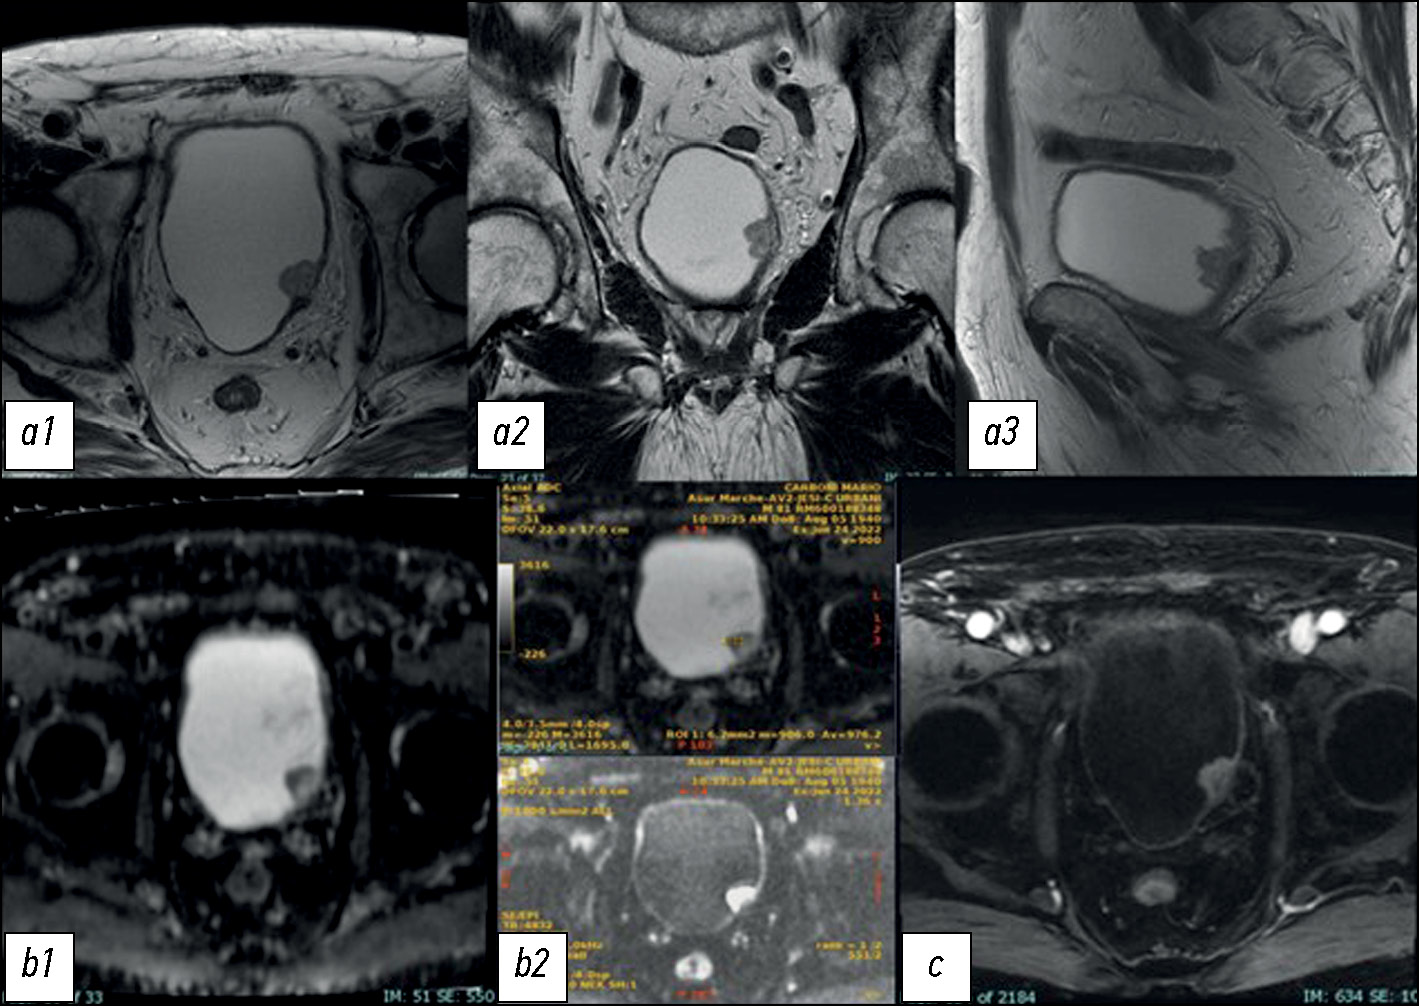

The development of the vesical imaging-reporting and data system (VI-RADS) score helps standardize the approach to MRI acquisition, interpretation, and reporting in patients diagnosed with BCa through TURBT. The score ranges from 1 to 5 and expresses the increasing risk of invasion of the detrusor muscle [6]. For accurate examination, the sequences include T2W, DWI/ADC, and DCE with each sequence generating a score of 1–5. T1W is not useful for differentiating MIBC from NMIBC because the detrusor muscle shows intermediate-signal intensity as well as a cancerous process [23].

Initially, the structural information in the T2W must be analyzed, evaluating the integrity of the muscular layer in T2W that should appear as homogeneously hypointense in contrast with a hyperintense signal of the bladder content. Then, the signal on DWI/ADC and DCE sequences must be evaluated. In tumors, the signal would appear hyperintense on DWI and hypointense on the ADC map, and there is an early enhancement of the inner layer. After obtaining information from each sequence, the combination of the different scores is compared to obtain the final VI-RADS score.

VI-RADS 1 is assigned when there is an interruption of the intensity signal line corresponding to the muscular layer in T2W. The maximum size reached from the lesion (sessile or vegetating) is 1 cm. VI-RADS 1 suggests an NMIBC.

VI-RADS 2 is assigned when there is an interruption of the intensity signal line but with a diameter >1 cm. The lesion could be associated with edema, appearing with a thickening line, and related to an increasing probability of invasion. VI-RADS 3 expresses a doubt: there is no clear disruption of the low-signal intensity of the muscular layer in T2W. VI-RADS 4 is assigned when there is a certain invasion of the muscular layer. VI-RADS 5 is assigned when the muscular layer invasion is associated with the involvement of the nearly adipose tissue.

In case of a discrepancy in results, the DWI/ADC map and DCE will prevail to downgrade and upgrade lesions [5].

In conclusion, MRI is rapidly becoming a leading imaging modality in BCa diagnostic workup, assessment of response to therapies, and longitudinal surveillance and plays an important role in treatment planning for BCa surgical and radiation therapy. Nevertheless, transurethral resection biopsy is required for tumor grading and cannot be replaced by MRI (Fig. 5 and 6).

Fig. 5. (a) Multiplanar T2W sequences showing a mass on the left posterior wall, >1 cm in size, with an intermediate signal of the muscular layer (VI-RADS 4). (b) DWI sequence and ADC maps showing a lesion with significantly limited diffusion, extending through the muscular layer. The low ADC value of approximately 0.9 × 10−3 mm2/sec denote malignancy (VI-RADS 4). (c, d) DCE sequence showing early and heterogeneous enhancement of the lesion, extending through the muscular layer (VI-RADS 4). The VI-RADS overall score was four. Image source: Eusebi Laura, Masino Federica, Gifuni Rossella, Fierro Davide, Michele Bertolotto, Cova Maria Assunta, Giuseppe Guglielmi. Role of Multiparametric-MRI in Bladder Cancer. Current Radiology Reports 11, 69–80 (2023). https://doi.org/10.1007/s40134-023-00412-5. This article is an open access article distributed under the terms and conditions of the Creative Commons Attribution (CC BY) license 4.0 (http://creativecommons.org/licenses/by/4.0/).

Fig. 6. (a) Multiplanar T2W sequences showing a mass, >1 cm, on the right lateral wall of the bladder dome, with an intermediate signal extending through the muscular layer and invading the perivesical adipose tissue (VI-RADS 5). (b) DWI sequence and c ADC map showing a significantly limited diffusion lesion extending through the muscular layer and invading the perivesical adipose tissue (VI-RADS 5). (c) DCE showing an early and heterogeneous improvement of the lesion extending through the muscular layer and the perivesical adipose tissue (VI-RADS 5). The VI-RADS overall score was five. Image source: Eusebi Laura, Masino Federica, Gifuni Rossella, Fierro Davide, Michele Bertolotto, Cova Maria Assunta, Giuseppe Guglielmi. Role of Multiparametric-MRI in Bladder Cancer. Current Radiology Reports 11, 69–80 (2023). https://doi.org/10.1007/s40134-023-00412-5. This article is an open access article distributed under the terms and conditions of the Creative Commons Attribution (CC BY) license 4.0 (http://creativecommons.org/licenses/by/4.0/).